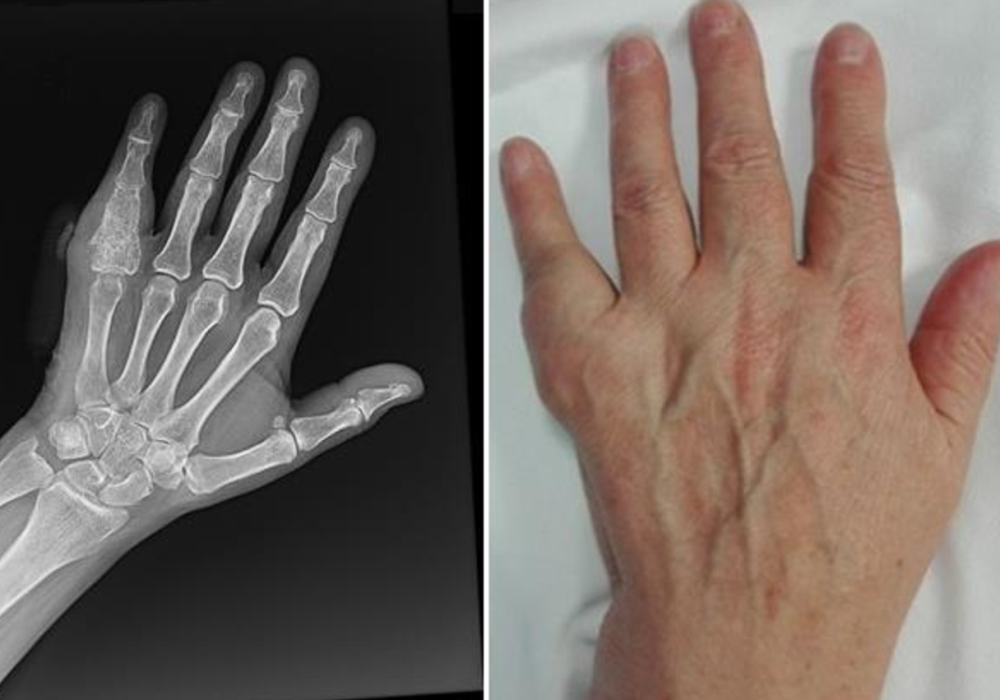

9 Enchondroma Hand

Enchondromas can occur in anyone but are most common in middle-aged patients. They are most often found in the small bones of the hand. In fact, enchondroma is the most common bone tumor of the hand. Enchondomas can also develop in the body’s long bones, such as the femur (thighbone), tibia (shinbone), and humerus (upper arm bone).

X-rays. X-rays provide images of dense structures such as bone. On X-rays, enchondromas appear as small (less than 5 cm), lobe-shaped, darkened tumors in the middle of the bone. They usually contain white spots or calcification within. The white areas of the tumor show a pattern of rings and arcs that indicates the tumor contains cartilage.